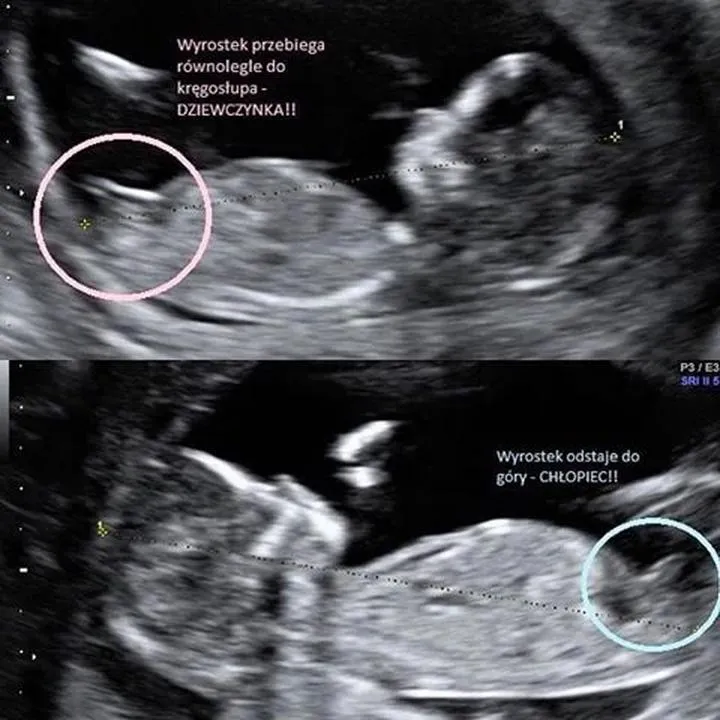

Zaskakujące fakty o tym, co wpływa na płeć dziecka

Jeśli kiedykolwiek zastanawialiście się, dlaczego w niektórych rodzinach panie rodzą jedynie dziewcz...